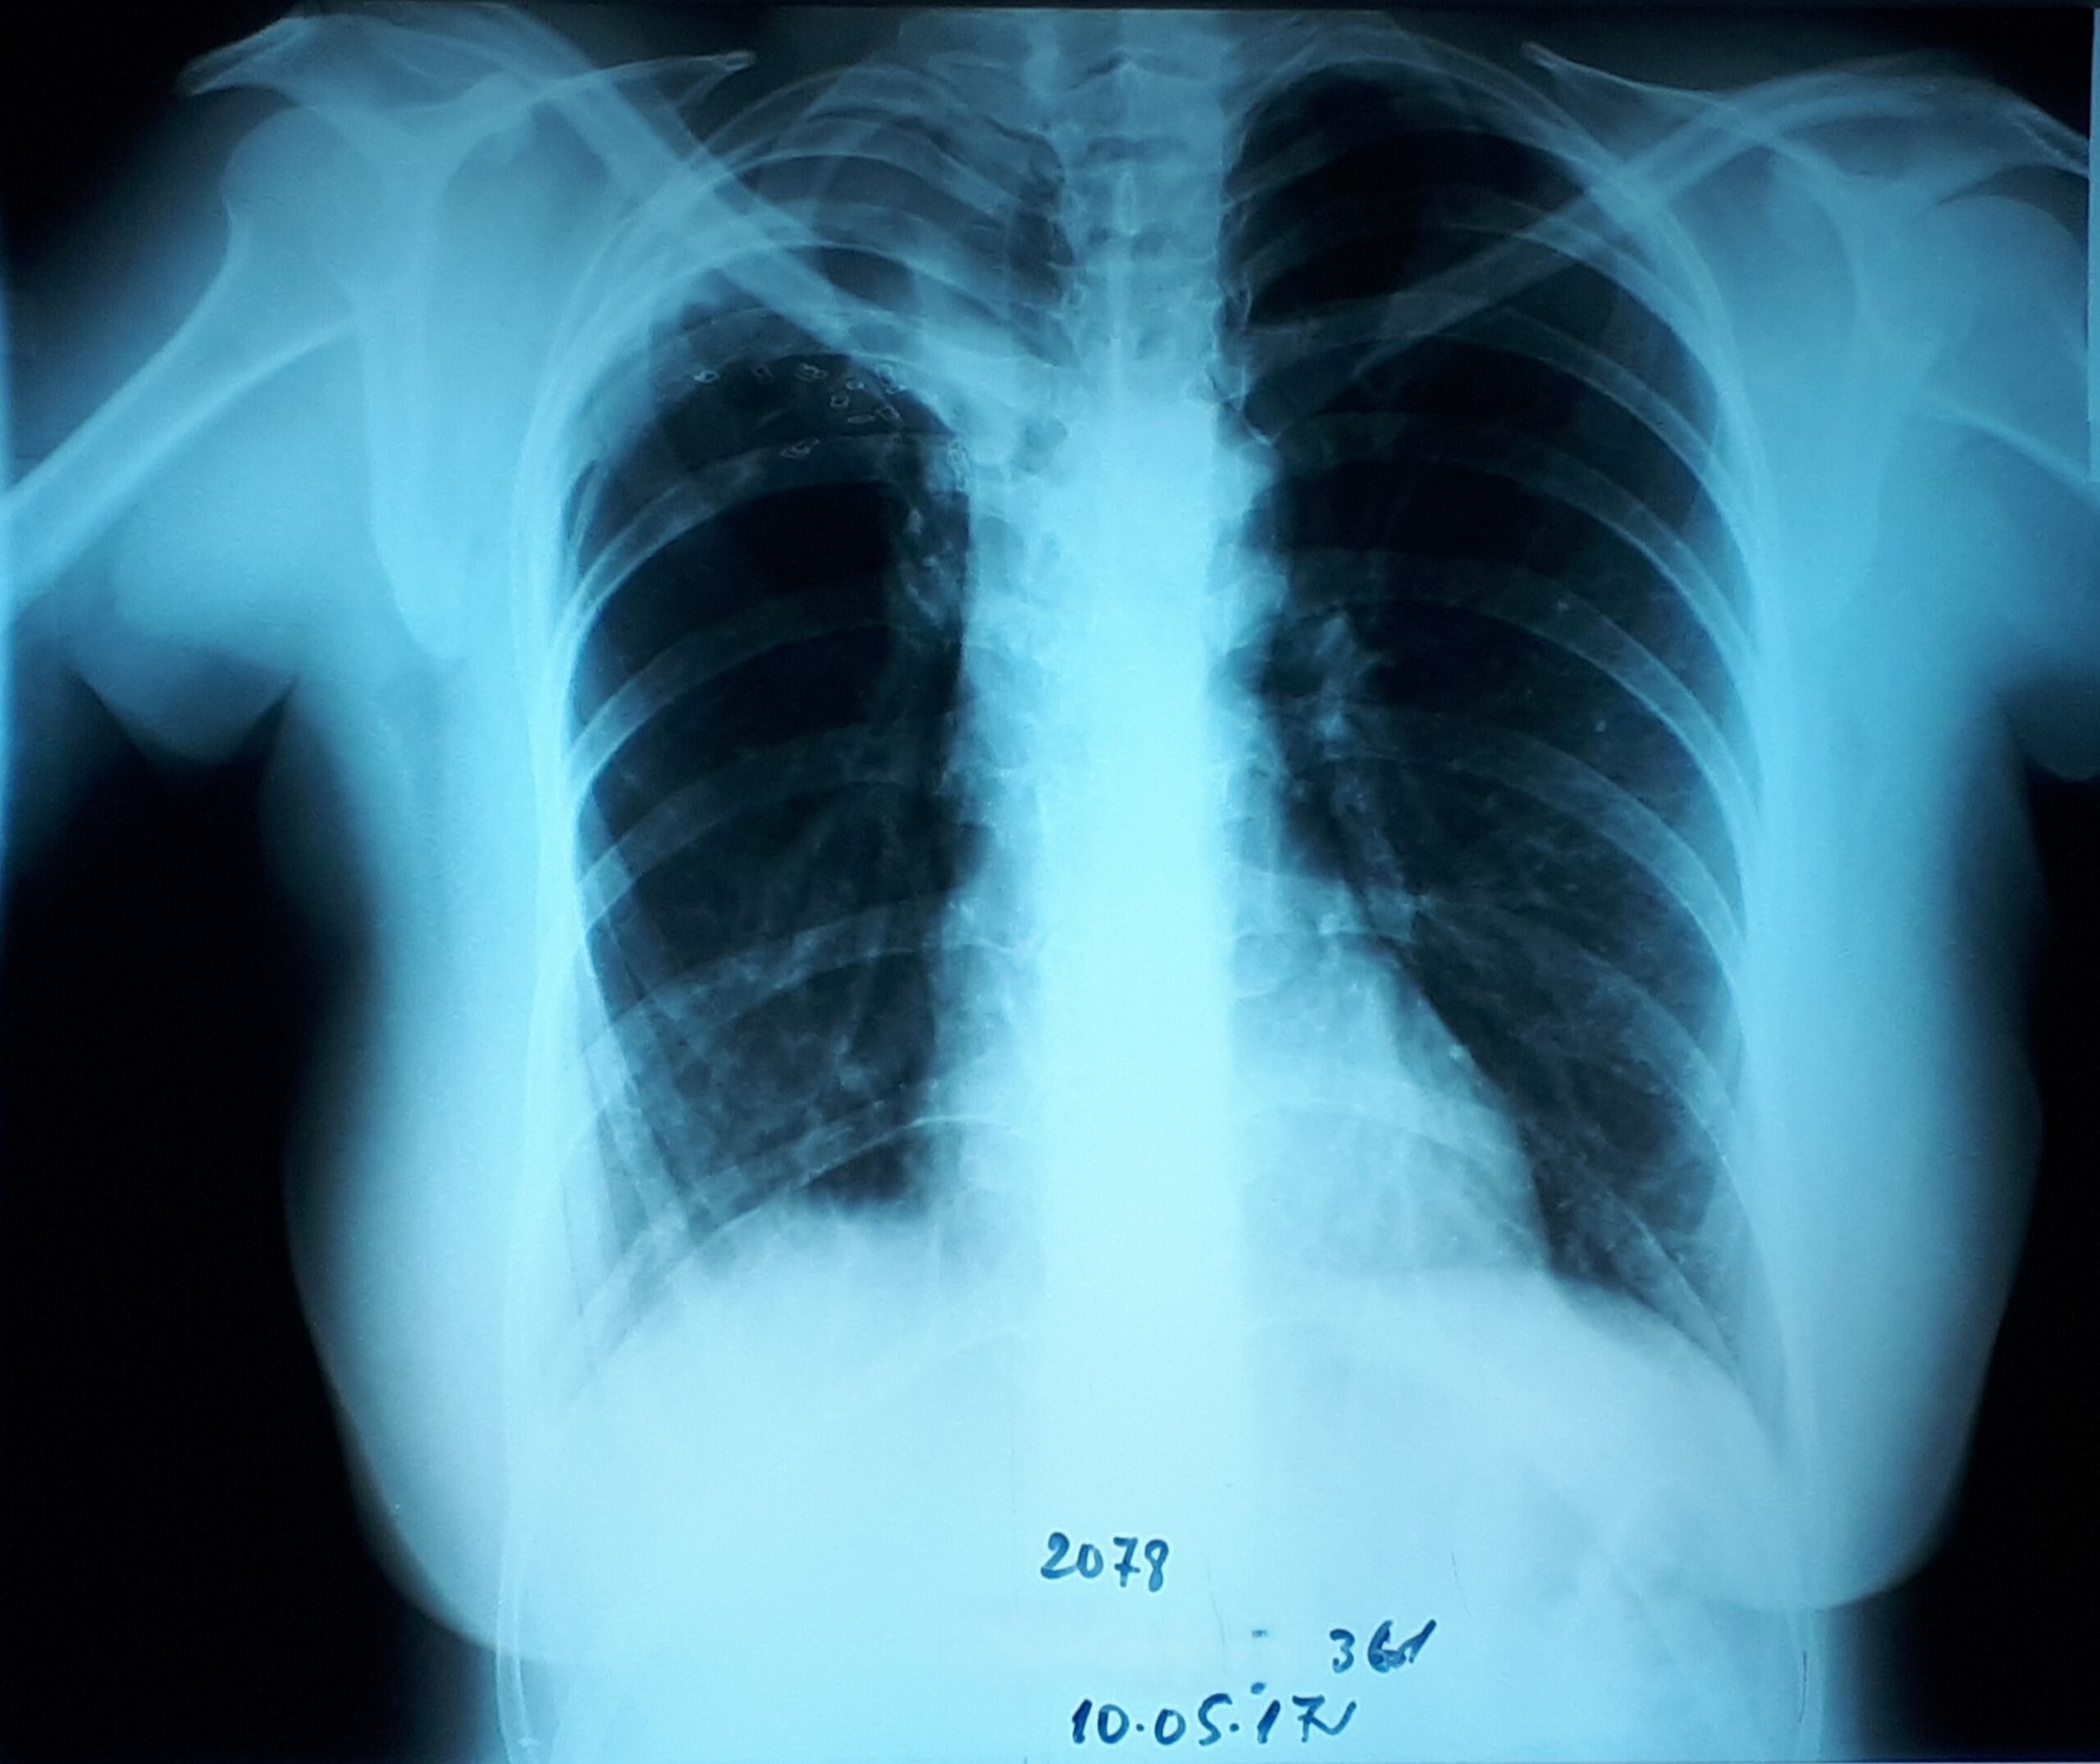

პაციენტი 37 წლის ქალი. 1997 წ-ს გაკეთებული აქვს მარჯვენა ზედა წილის რეზექცია ფილტვის ტუბერკულოზის გამო. წლების განმავლობაში აქვს გამწვავებები, რაც გამოიხატება მაღალი ცხელებით, ხველით, დიდი რაოდენობით სისხლნარევი, მძაფრი სუნის მქონე ნახველის გამოყოფით. რენტგენოლოგიურად ინახა დიდი ზომის ღრუ მარჯვენა ფილტვის ზედა ველში. ბრონქოსკოპიით ინახა დიდი ზომის მარჯვენა ზ/წილოვანი ბრონქის ტაკვის ფისტულა. ტაკვის სიგრძე იძლეოდა ბლოკატორის ჩადგმის შესაძლებლობას. რიგიდული ბრონქოსკოპით მარჯვენა ზ/წილოვან ბრონქში ჩაიდგა MEDLUNG-ის ბლოკატორი N13. რამოდენიმე საათში საჭირო გახდა ბლოკატორის გამოცვლა ნაკლებ (N12) ზომაზე განვითარებული მარჯვენა ქვედა წილის ატელექტაზის გამო. მანიპულაციის შემდეგ პაციენტს შეუწყდა სისხლნარევი და ჩირქოვანი სეკრეტი. 10 თვის შემდეგ საკონტროლო გამოკვლევით ღრუს ადგილას დაფიქსირდა ფიბროთორაქსი. უახლოეს მომავალში, გულმკერდის კტ კვლევის შემდეგ, იგეგმება ბლოკატორის ამოღება.